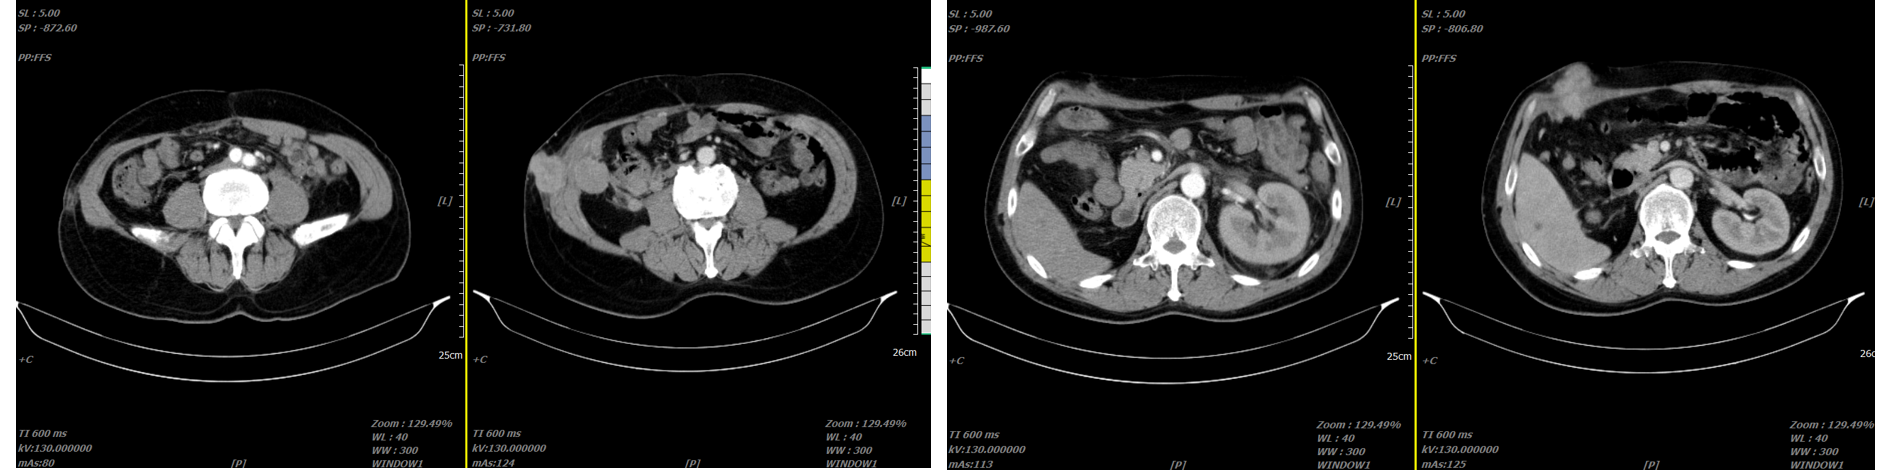

患者一月余前检查时发现右肾肿瘤,伴有肉眼血尿,尿频,尿急,尿痛,伴有腰痛,无发热等其他特殊不适,于当地医院超声检查提示右肾占位性病变,考虑肿瘤,为求进一步诊治于我院就诊,行肾脏增强CT检查提示右肾肿瘤,考虑肾透明细胞癌可能性大,肿瘤突破被膜,肾周受侵。病程中饮食睡眠欠佳,体重减轻近10kg。

右肾肿瘤 9.8cm*7.9cm

肾周受侵

肾门可见肿大淋巴结

未见明显远处转移

右肾肿瘤(肾透明细胞癌可能极大)III期 T3NxM0 IMDC 中危组。

行经腹右肾根切除术治疗。术后病理:透明细胞性肾细胞癌,肿瘤侵犯肾纤维被膜,局部紧邻肾周脂肪几肾盂,未侵犯肾窦脂肪。T3N0M1。